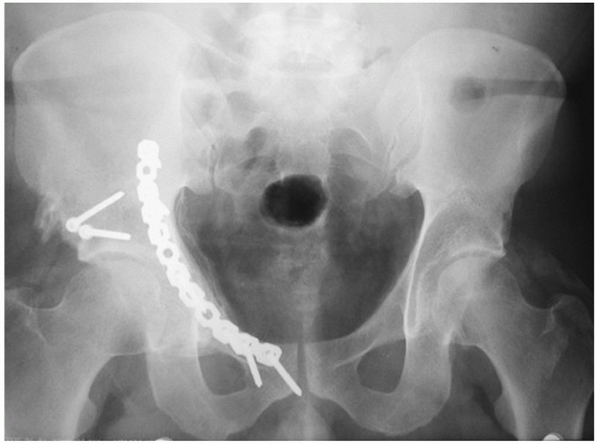

FIGURE 45-30 Radiographic appearance of a both-column fracture. A.

Despite disruption of all six of the radiograph landmarks, the femoral head is seen to remain congruent to the roof and anterior column fragment. The position of the head on the anteroposterior radiograph is medialized as well as superiorly displaced. Fracture of the contralateral pubic body because of the displacement of the superior pubic ramus fragment is noted. B. The obturator oblique demonstrates the spur sign (arrowhead) as well as confirming the congruence between the femoral head and acetabulum. C. The iliac oblique view reveals loss of congruence between the femoral head and the posterior column; therefore, this fracture is indicated for surgical treatment. D. The computed tomography section shows the anterior column (white arrow), the superior extent of the posterior column (white arrowhead), the spur sign of the iliac wing (black arrow), and a large posterior wall fracture (black arrowhead). (Copyright Berton R. Moed, MD.) |

congruent to, the femoral head (Fig. 45-29). This creates a situation unique to both-column fractures that is known as “secondary congruence.”78,147 The radiograph “spur sign,” when present, is pathognomonic for the associated both-column fracture.78

This is seen best on the obturator oblique projection and represents

the external cortex of the most caudal portion of the intact ilium (Fig. 45-30).

surface remains intact with the ilium.78 It is also common for the both-column fracture to have a posterior superior wall fracture component (Figs. 45-30 and 45-31).